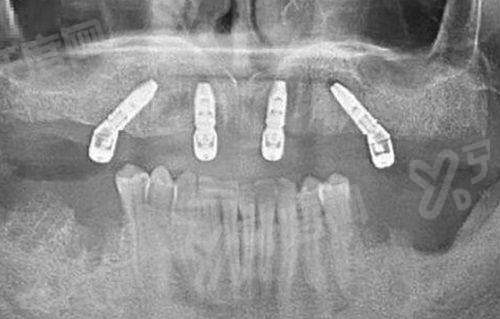

(一)数字化导板种植技术实操

1、医院采用 CBCT 三维影像扫描结合计算机辅助设计,在术前生成精细的种植导板,将种植体植入误差控制在毫米级别。

2、这种技术实现了微创切口操作,无需大面积翻瓣,术后肿胀轻、修复快,特别适合高龄或缺骨量有限的复杂病例。

3、全程可视化监控让患者对治疗过程心中有数,医生能实时调整角度和深度,确保了手术的安心性和长期稳定性。